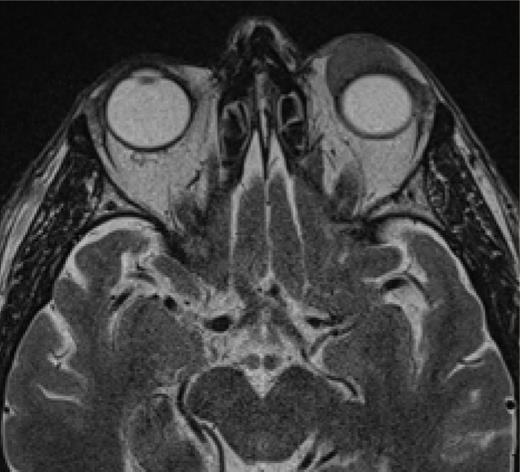

Axial MRI showing a lesion in the extraconal compartment of the left orbit.

A 62-year-old man presented with progressive ptosis of the left eyelid, which he had been experiencing for the past year. He had no other symptoms or significant medical history. Physical examination revealed a firm mass below the left supraorbital rim, with secondary mechanical ptosis (Figure 1). Magnetic resonance imaging (MRI) revealed an extraconal, expansile lesion with well-defined edges at the level of the left upper eyelid, along with predominantly hypointense homogeneous signal intensity in T1 and T2 sequences showing restricted diffusion (Figure 2). Analysis of the biopsy specimen revealed a diffuse pattern of small lymphocyte proliferation and monomorphic cytology consisting predominantly of centrocyte-like cells of B-cell lineage (CD20+). Cyclin D1 and SOX11 expression were detected, although the specimen was negative for BCL6, CD5, CD10, and CD23 expression (Figure 3). The neoplastic cells exhibited restricted expression of kappa light chain, an unremarkable pattern of p53 expression (wild-type pattern), and a low Ki67 proliferation index. Fluorescence in situ hybridization detected chromosomal rearrangement involving CCND1 at 11q13.